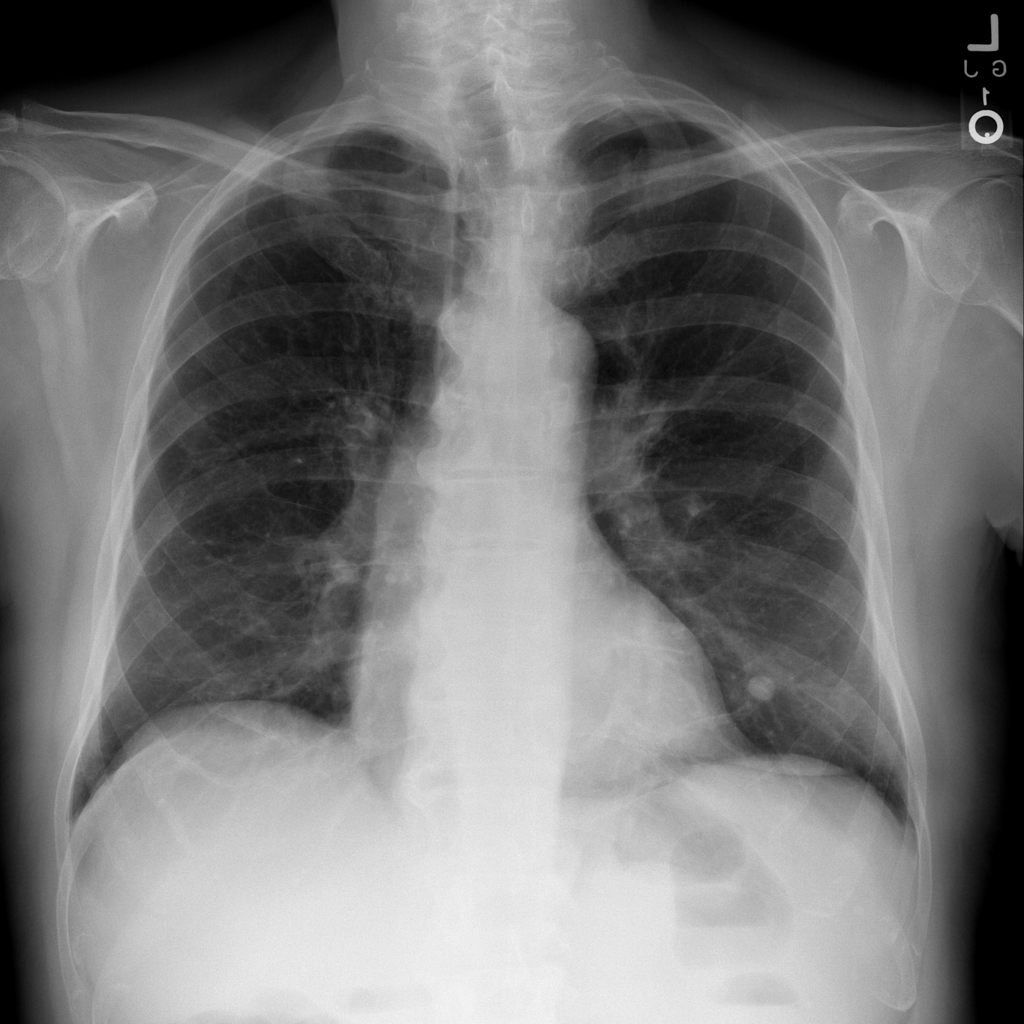

Nodule

A nodule is a small rounded opacity in the lung or chest field. It is a descriptive imaging finding that can be benign or more concerning depending on size, appearance, and context.

Showing up to 90 reference images for Nodule.

PAT-F3E7 · IMG-002Nodule

PAT-F3E7 · IMG-002

PA